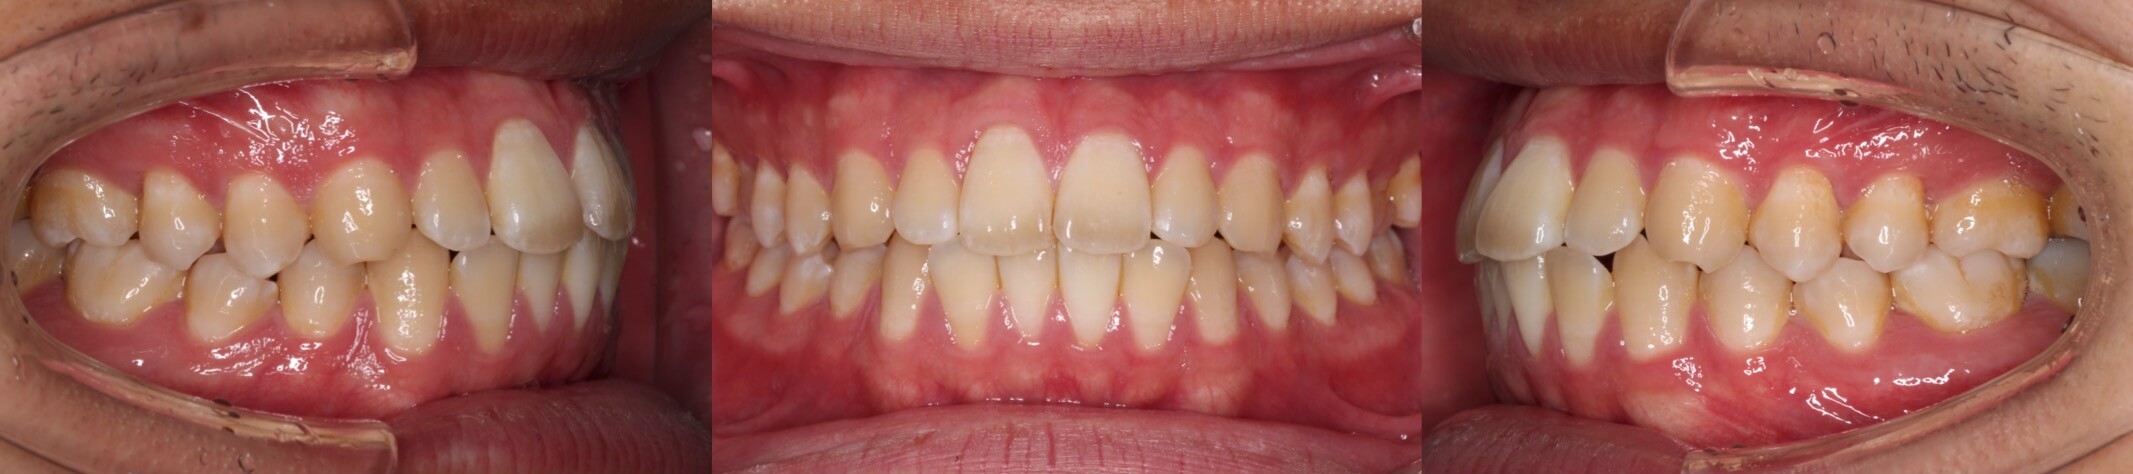

<軽度のボーイングエフェクトは唇側矯正であれば容易に改善可能>

重度のボーイングエフェクトが発生した場合はリカバリー治療を行わなくてはなりません。唇側矯正治療を行なっている場合は、軽度〜中程度の問題であることが多く、前歯を後方移動させる力を解除するだけで、時間の経過とともに治ってくることが多いです。